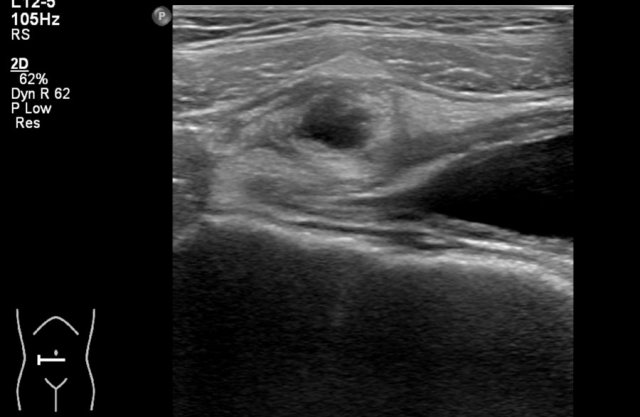

Here an antenatally detected cyst, confirmed after birth in a newborn girl.

A cyst with a fluid-fluid level is seen.

At operation a torsion of the left ovary was found.